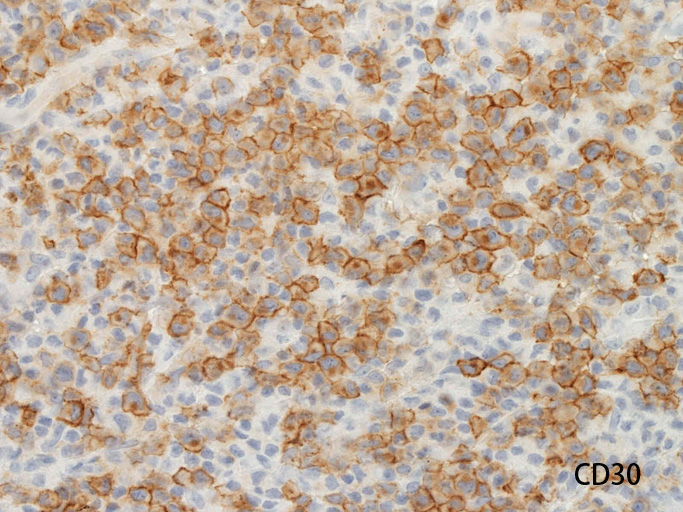

ALK/p80が細胞質・核に陽性となる。大型類円形核の細胞以外に, やや小型の類円形細胞に陽性細胞が認められるようです。背景細胞の多くはALK陰性。

ALKは核, 細胞質いずれにもびまん性に染まるパターンです。CD3, CD20は陰性でnull cellの様ですがCD45RO(UCHL-1)が膜に陽性となっています。